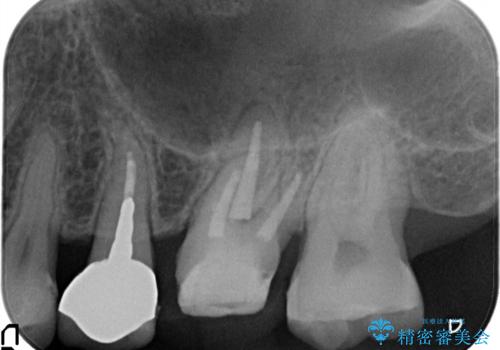

- 以前から奥歯に違和感があることを主訴に来院されました。歯肉にサイナストラクトを認めたため、再根管治療を行った後オールセラミッククラウンにて修復治療を行いました。根管治療は林先生に依頼しております。